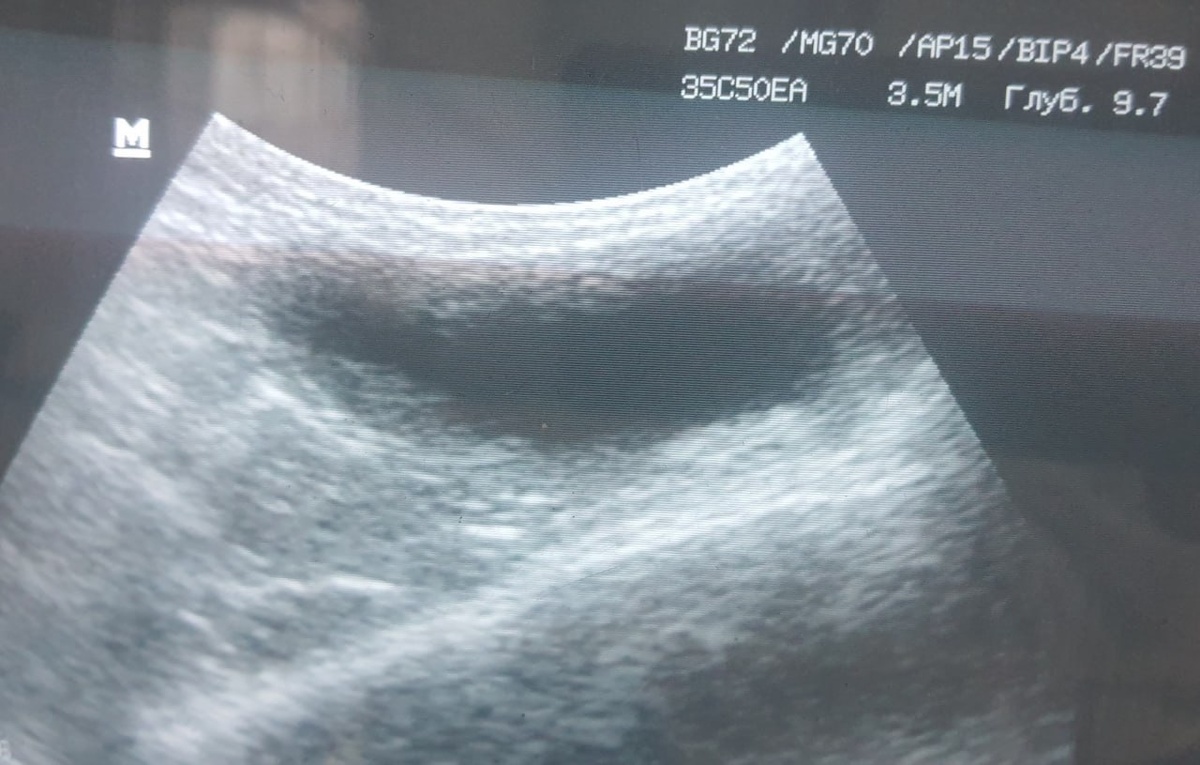

Утолщенная, неоднородная стенка мочевого пузыря, наличие гиперэхогенных структур (камни, "песок") в мочевом пузыре, гиперэхогенное содержимое в расширенной уретре. Дифференциальный диагноз: хронический цистит (идиопатический, бактериальный), мочекаменная болезнь (уролитиаз), обструкция уретры (закупорка пробкой, песком), дисфункция нижних мочевых путей кошек (FIC) — "стрессовый цистит". НЕОТЛОЖНАЯ ПОМОЩЬ В КЛИНИКЕ - срочная катетеризация, инфузионная терапия, забор анализов мочи и крови, снятие симптоматики и лечение основного заболевания. Работаем.